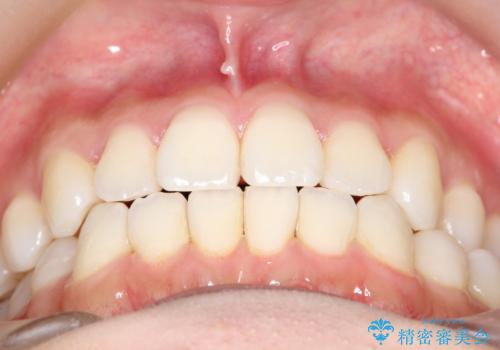

軽度の前歯のガタガタをインビザラインでの目立たない矯正

- 前歯のガタガタを主訴に来院されました。

軽度であったため、枚数制限のあるタイプのインビザラインのプランで治療することとしました。

軽度のガタガタを目立たずに手軽に矯正できるのもマウスピース矯正の魅力といえます。